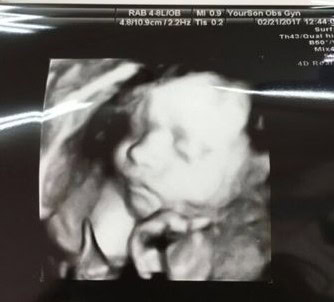

而且診所的超音波都超清楚的

孕媽咪在意的超音波相片也是媽媽們每次產檢的期待,但醫院可不是沒每次都照,